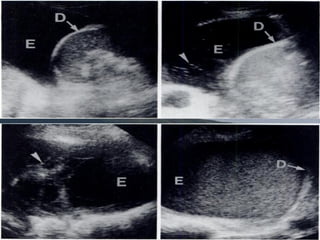

Tissue pattern representative of Alveolar

Consolidation

Presence of hyperechoic punctiform

images

imagesrepresentative of air bronchogramsrepresentative of air bronchograms

Pleural

effusion